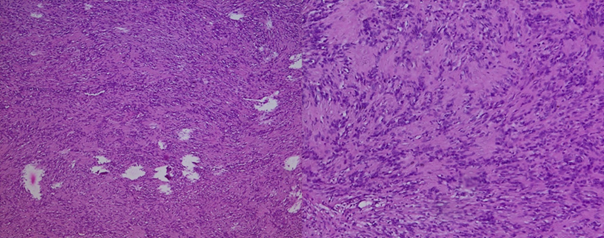

The histology report indicates

a nodular mass with necrotic rearrangement. The tumor proliferation exhibited

spindle-shaped cells with elongation and an absence of mitosis. The diagnosis

of neurilemoma was favored2,3 (Figure 4).

Figure 4: H&E stained sections of the surgically resected

tumor (×20 and ×40 magnification) revealed cytological bland spindle cells with

vague nuclear palisading and a fibrillary background.